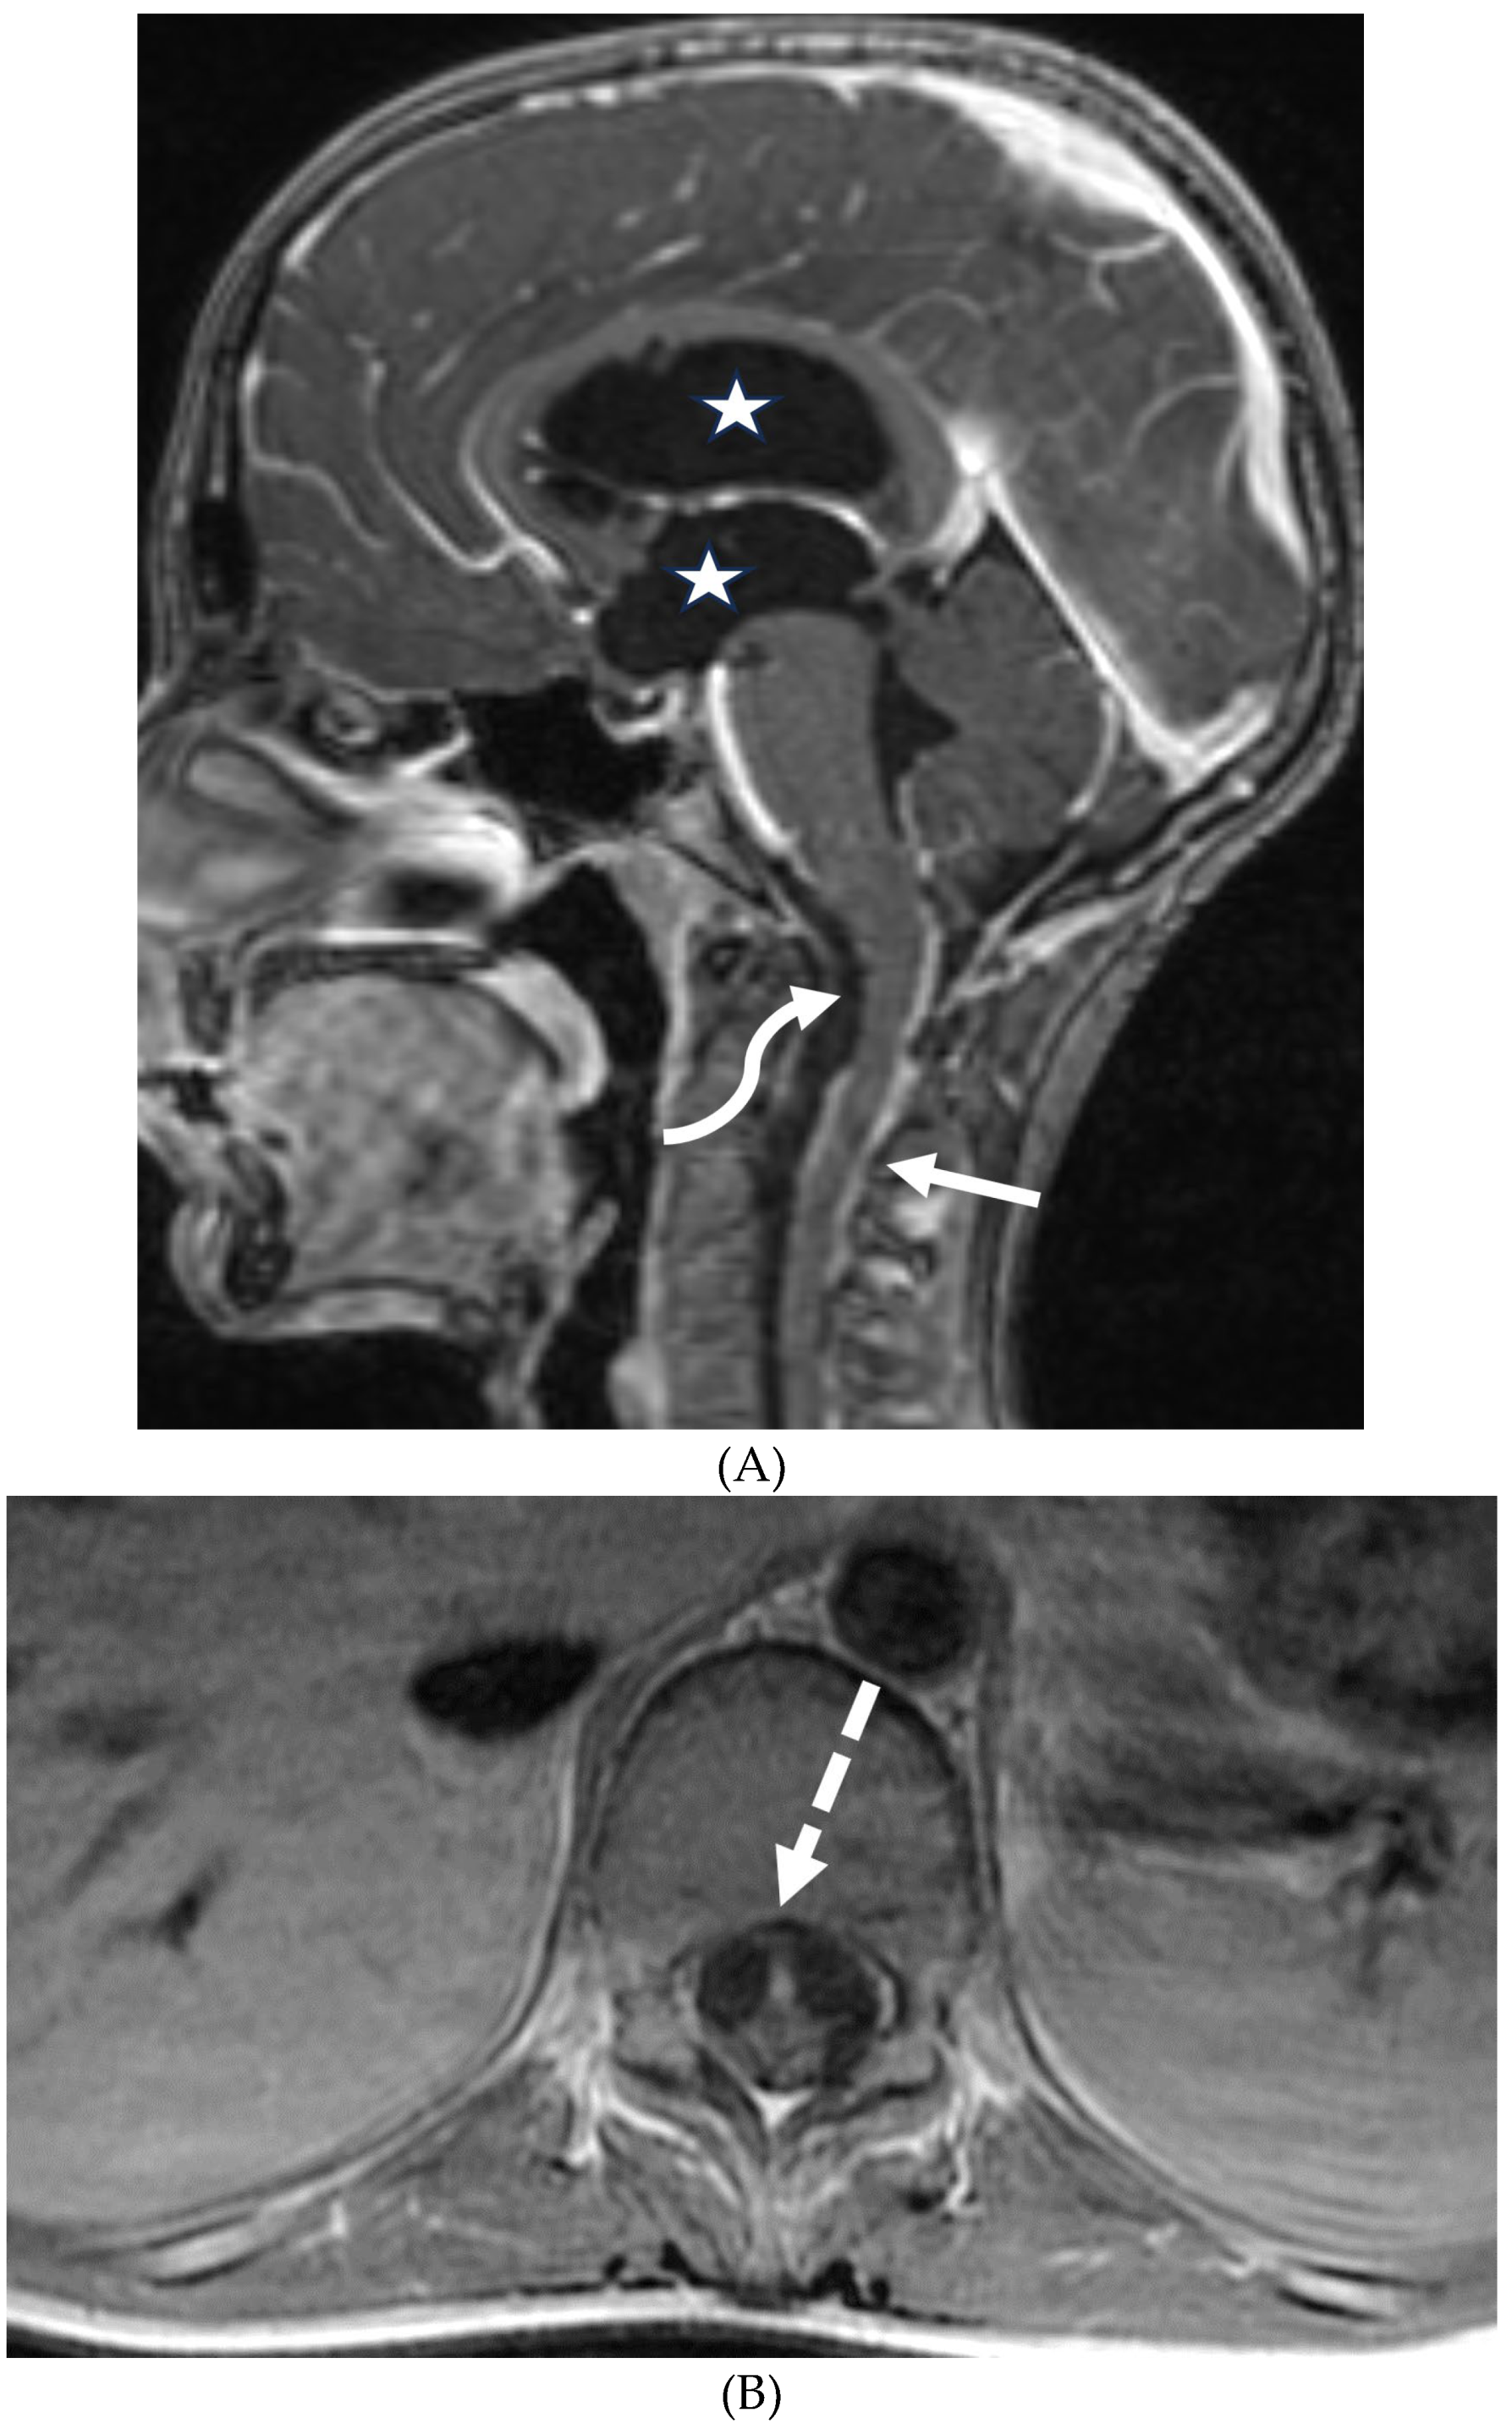

- Karlowee, V., Kolakshyapati, M., Amatya, V.J. et al. Diffuse leptomeningeal glioneuronal tumor (DLGNT) mimicking Whipple’s disease: a case report and literature review. Childs Nerv Syst 33, 1411–1414 (2017). [CrossRef]

- Rodriguez FJ, Perry A, Rosenblum MK, Krawitz S, Cohen KJ, Lin D, Mosier S, Lin MT, Eberhart CG, Burger PC. Disseminated oligodendroglial-like leptomeningeal tumor of childhood: a distinctive clinicopathologic entity. Acta Neuropathol. 2012 Nov;124(5):627-41. Epub 2012 Sep 1. PMID: 22941225. [CrossRef]

- Lakhani DA, Mankad K, Chhabda S, Feizi P, Patel R, Sarma A, Pruthi S. Diffuse Leptomeningeal Glioneuronal Tumor of Childhood. AJNR Am J Neuroradiol. 2020 Nov;41(11):2155-2159. Epub 2020 Sep 10. PMID: 32912870; PMCID: PMC7658820. [CrossRef]

- Gardiman MP, Fassan M, Orvieto E, D'Avella D, Denaro L, Calderone M, Severino M, Scarsello G, Viscardi E, Perilongo G. Diffuse leptomeningeal glioneuronal tumors: a new entity? Brain Pathol. 2010 Mar;20(2):361-6. Epub 2009 May 22. PMID: 19486008; PMCID: PMC8094733. [CrossRef]

- Jiang H, Qiu L, Song J, Xu D, Sun L, Feng Y, Zhao J, Qian J, Yu Z, Peng J. Clinical progression, pathological characteristics, and radiological findings in children with diffuse leptomeningeal glioneuronal tumors: A systematic review. Front Oncol. 2022 Sep 16;12:970076. PMID: 36185310; PMCID: PMC9525023. [CrossRef]